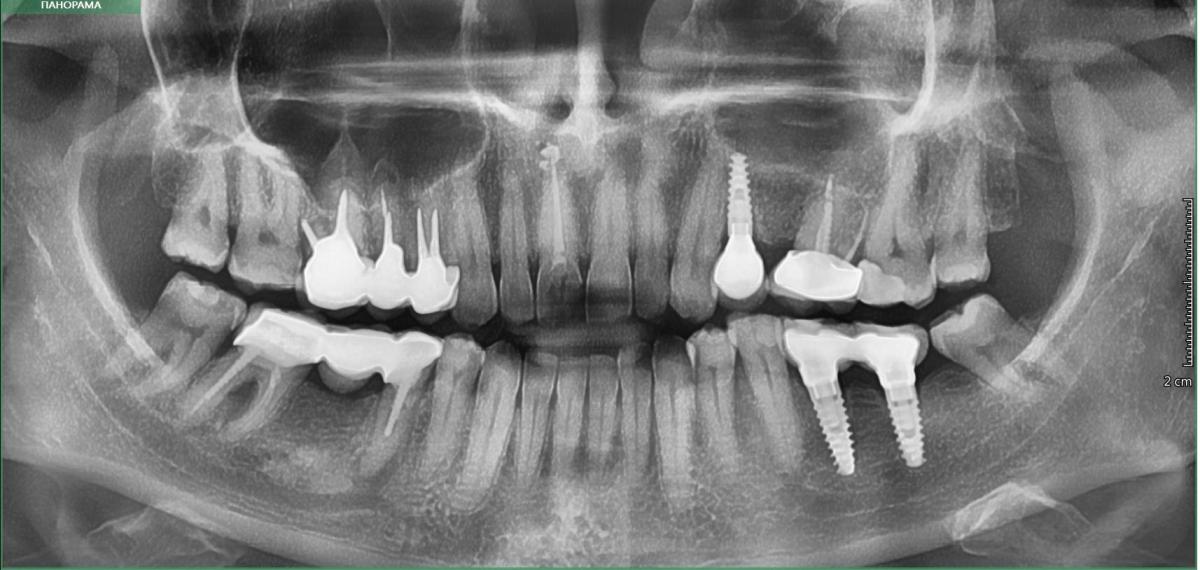

10 лет назад были установлены коронки, справа вверху и внизу. Полгода назад по назначению стоматолога сделала снимок и в корнях под коронками обнаружились кисты. Стоматолог рекомендовала наблюдать. Другой врач так же сказал пока не трогать. И оба как-то неуверенно (.

- на каких зубах эти кисты? (не понимаю снимок)

По симптомам, о которых Вы рассказываете, скорее всего причина не в зубах "с кистами"... Ищите проблему на других зубах!

Реакция на холодное не связана с наличием кистогранулем на корнях зубов,а вот боль при накусывании да.

По этому снимку определённо есть проблемы с зубами(помечены маркерами)Нижний мост придется снимать,47 необходимо перелечить каналы,а вот 45 ,на корне которого киста, возможно придется удалять(?)

На верхних зубах ситуация сложнее,т.к.16,15 и 14 покрыты коронками,спаянными вместе и к тому же зубы со шрифтами(если проблема сохраняется тоже в них,то прогноз скорее всего удаление,поэтому врачи Вам и посоветовали подождать)

Добавлю,что если 45 ,после снятия моста и благополучного удаления штифта,возможно перелечить,то перелечивайте и тогда заново можно протезировать.